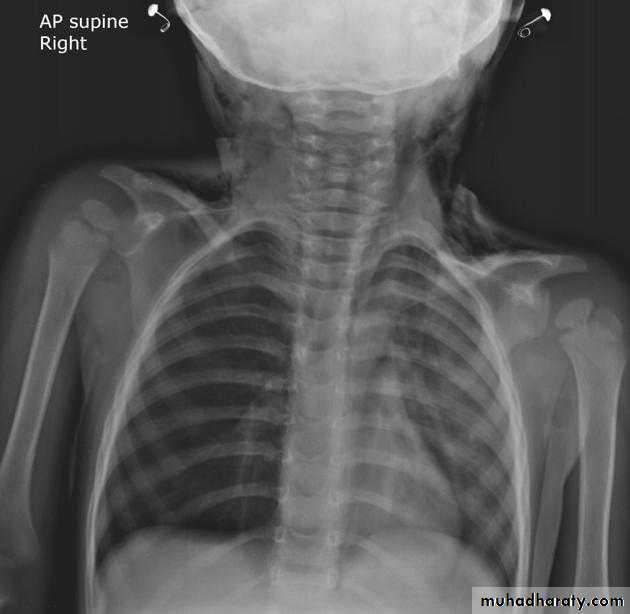

Unilateral obstructive emphysemaunilateral emphysema or atelectasis are the most common findings; only uncommonly will a radio-opaque foreign body be demonstrated ,Aspirated foreign bodies have a predominance for the right tracheo bronchial tree.